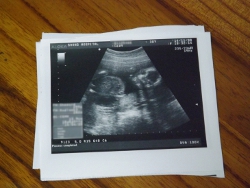

醫學用的超音波診斷系統是利用超音波本身的能量特性,藉由人體組織對聲阻的差異,產生能量反射、散射或吸收等不同的結果,反映出人體內組織的狀況,除了上述的婦產科超音波胎兒檢察之外,還可以利用於檢查人體其他軟組織病變,例如肌肉外傷、軟組織腫瘤、肩關節 ... 等。